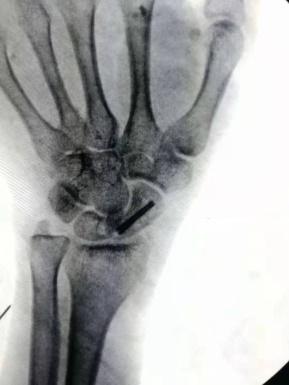

術(shù)前影像資料,舟骨腰部偏近極的骨折

四川友誼醫(yī)院骨科最近成功開展了一例“微創(chuàng)舟骨骨折空心釘固定手術(shù)”。患者曹某某,女,52歲。因“外傷致左腕關(guān)節(jié)疼痛、活動受限1小時”入院。輔助檢查:左腕關(guān)節(jié)CT平掃:左腕舟骨骨折。226日行“左腕舟骨骨折切開復位內(nèi)固定術(shù)”。術(shù)后復查骨折復位良好,內(nèi)固定穩(wěn)定可靠。左腕關(guān)節(jié)活動良好。